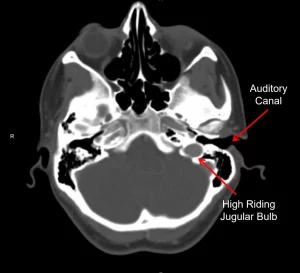

Whooshing in Ear from a Venous Hum

A vein close to the auditory canal might cause a constant hum. That is known as a venous hum. One reason is a high-riding jugular bulb. In select cases, ligating the jugular vein will resolve the tinnitus.